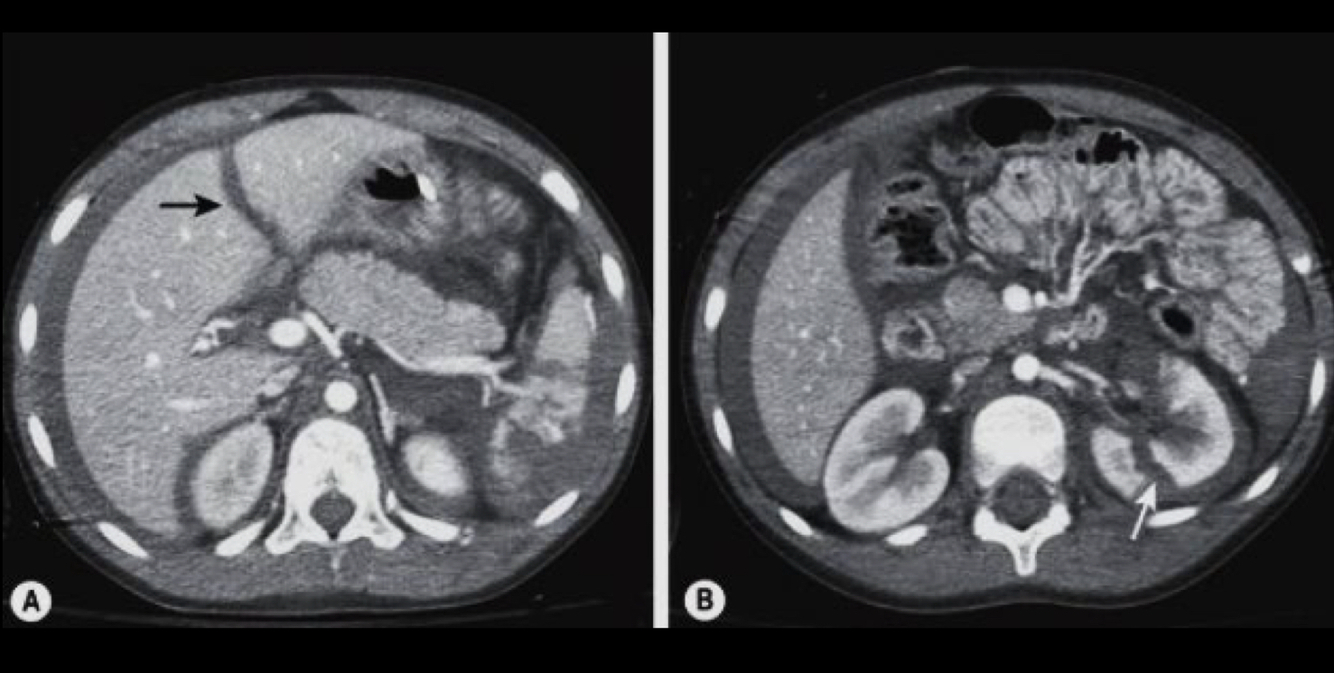

Que es?

A

TC trauma de abd cerrado

se ve

higado, bazo, pancreas, riñones

liquido, hemorragia, aire, laceraciones, infartos